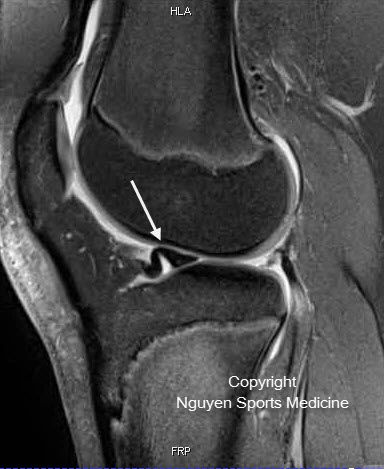

- Meniscus Surgery

- Meniscus Surgery 2